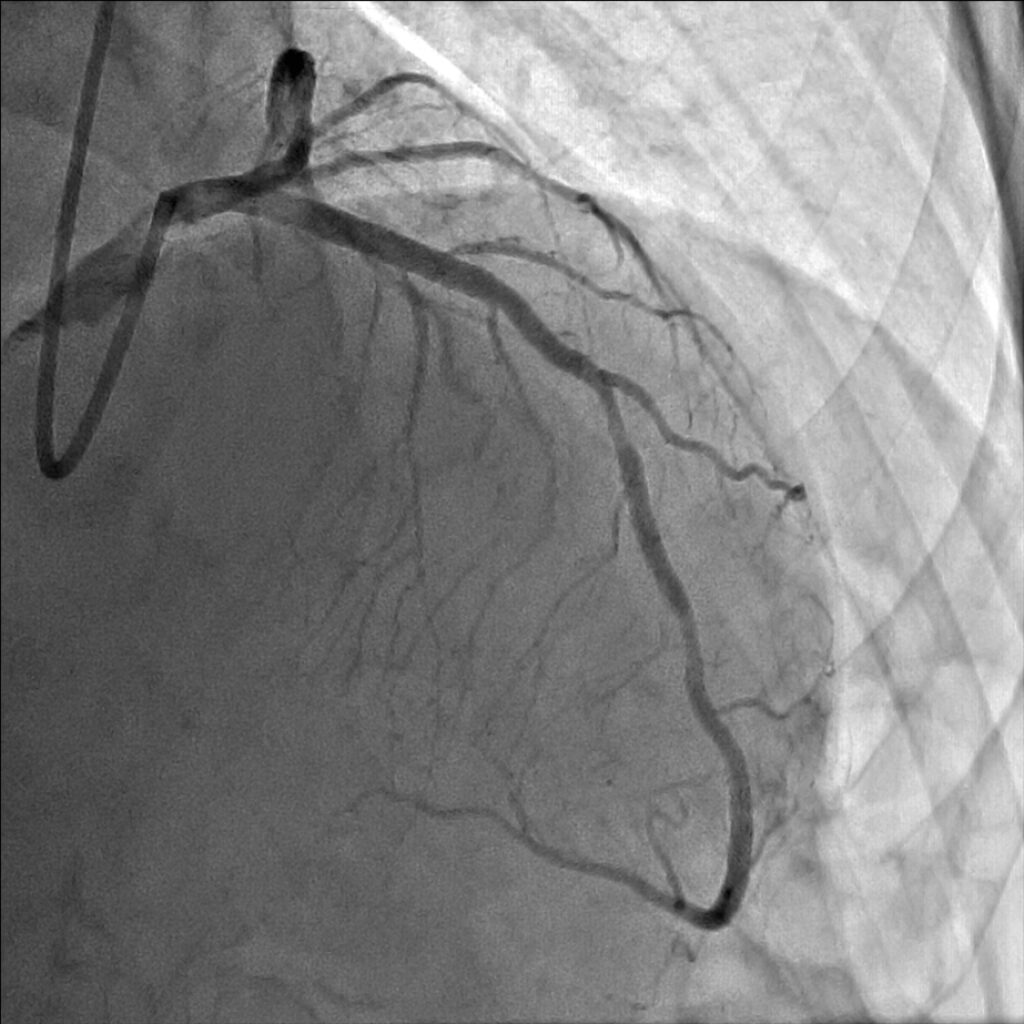

妻の勧めで近所の医院を受診しました。安静時心電図検査では何の異常もなかったのですが、念のためにと私の外来を紹介されました。ベルトコンベアーの上を歩く運動負荷心電図検査でいつもと同じような症状を覚え、心電図に異常が出現しました。私は労作性狭心症と診断しました。手首からカテーテルを挿入した冠動脈造影検査で、一番大きな冠動脈枝の近位部に高度な狭窄が見つかりました。後日、風船とステントを用い、狭窄を開大しました。症状は完全に消失し、今は農作業に精を出しています。

治療はカテーテルを使い風船やステントで狭窄部を拡張し、血液の流れをよくすることが一般的です。冠動脈の全ての枝に狭窄がある方、あるいは左主幹部と呼ばれる最も太い血管と他の枝に病気が重複している重症な方等には冠動脈バイパス手術をお勧めしています。しかし、症状が無い方や心筋虚血を心電図等で客観的に認めない方は、冠動脈に狭窄があっても、こうした治療をせず悪玉コレステロールを下げる、高血圧をコントロールする、禁煙をする、糖尿病のコントロール等の冠動脈硬化の危険因子を治療することで経過をみることも多いです。